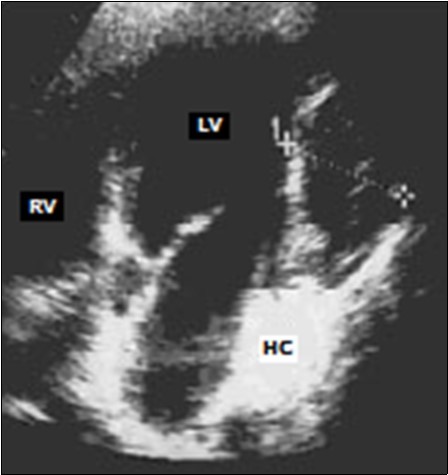

Transthoracic echocardiography showed an intra-myocardial mass localized in the infero-posterior wall of the left ventricular. This mass was well-defined, oval-shaped, echogenic, heterogeneous, measuring 37 × 62mm long axes, and largely calcified (Figure 2).

Figure 2.Trans-thoracic echocardiography: echogenic, heterogeneous mass of the infero-posterior wall of the left ventricle (LV: left ventricle, RV: right ventricle, HC: hydatid cyst).

Echocardiography (trans-thoracic and/or trans-oesophageal) remains the test of choice for the positive diagnosis of cardiac HC 18. It makes it possible to specify the seat of the cyst at the level of the heart and its relation with the adjacent structures as well as its repercussion on the cardiac cavities 18, 25. The cardiac HC is often unique 21 and more rarely multiple 16.